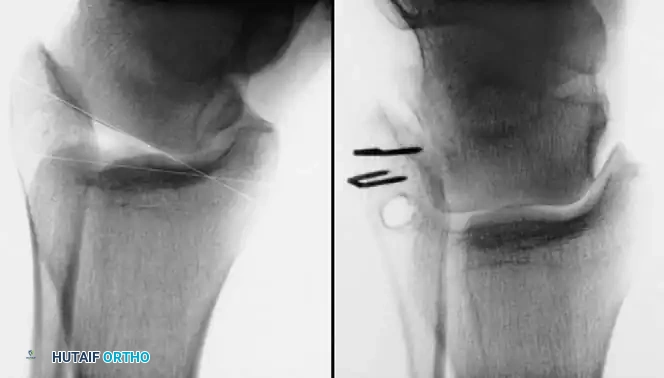

Repair of Acute Rupture of the Deltoid Ligament

Isolated surgical repair of the deltoid ligament is rarely indicated. However, in the setting of a bimalleolar equivalent fracture (fibular fracture with complete deltoid rupture and lateral talar shift), the deltoid may become incarcerated within the medial clear space, preventing anatomic reduction of the mortise.

Surgical Technique:

1. A medial longitudinal incision is made centered over the medial malleolus.

2. The joint is cleared of hematoma and the interposed deltoid ligament is extracted from the mortise.

3. The deep posterior tibiotalar ligament is repaired first using suture anchors placed into the medial talar body or medial malleolus.

4. The superficial deltoid is then imbricated and repaired in a pants-over-vest fashion.